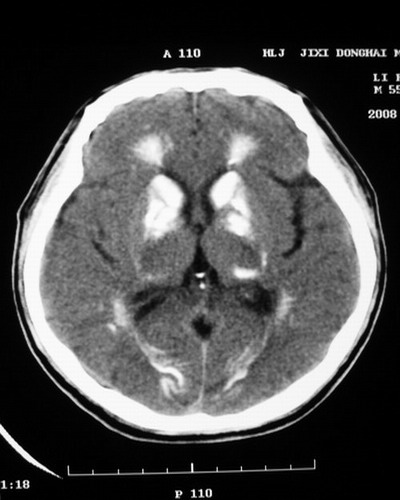

以下是引用随光逐影在2008-1-14 17:26:00的发言:[br]考虑为:甲状旁腺功能低下。需与fahr`s病相鉴别。建议:实验室检查。